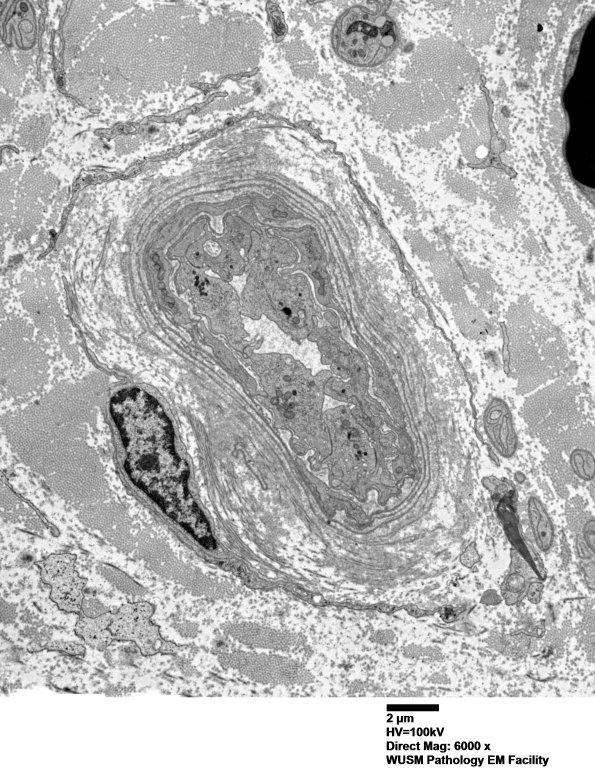

Washington University Experience | VASCULAR | Hypoxia-Ischemia, fetal-neonatal | White Matter | 16B1 (Case 16) HIEM EM017 - Copy

16B1 (Case 16) HIEM EM017 - Copy